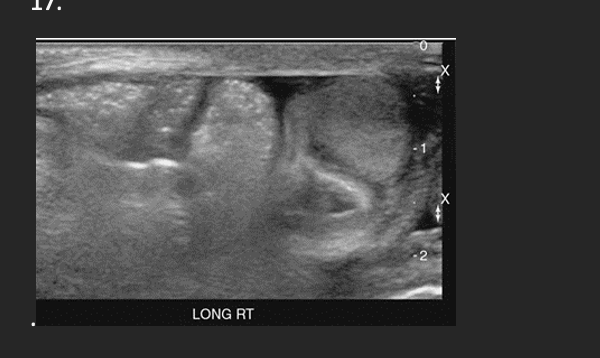

A patient presents with a small mass palpated in a recent physical exam and normal lab values. A mass is identified in the inferior portion of the right thyroid lobe. On the basis of this clinical history, the sonographic findings are most suspicious for a

B. Adenoma